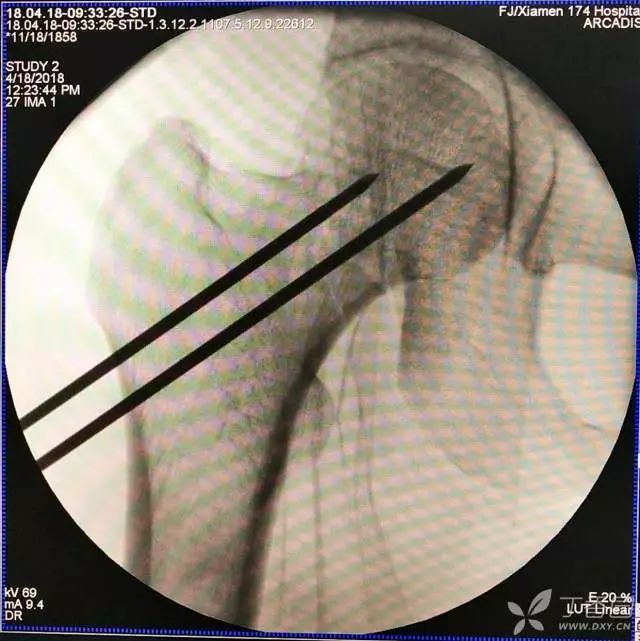

4. 先体外放置一枚导针导引进针方向

7. 摆 4 字位检查侧位导针的位置是否恰当

笔者的部分股骨颈骨折病例在牵引床被占用的情况下,会选择在普通手术床完成手术,所以必须打上三枚克氏针后再摆 4 字位透视侧位。

摆体位时,笔者首先会垫枕消除前倾角。然后放体外克氏针判断大致的进针方向(这个步骤是在消毒完毕,骨折复位后再做。如果没复位,笔者选择直接切开)。